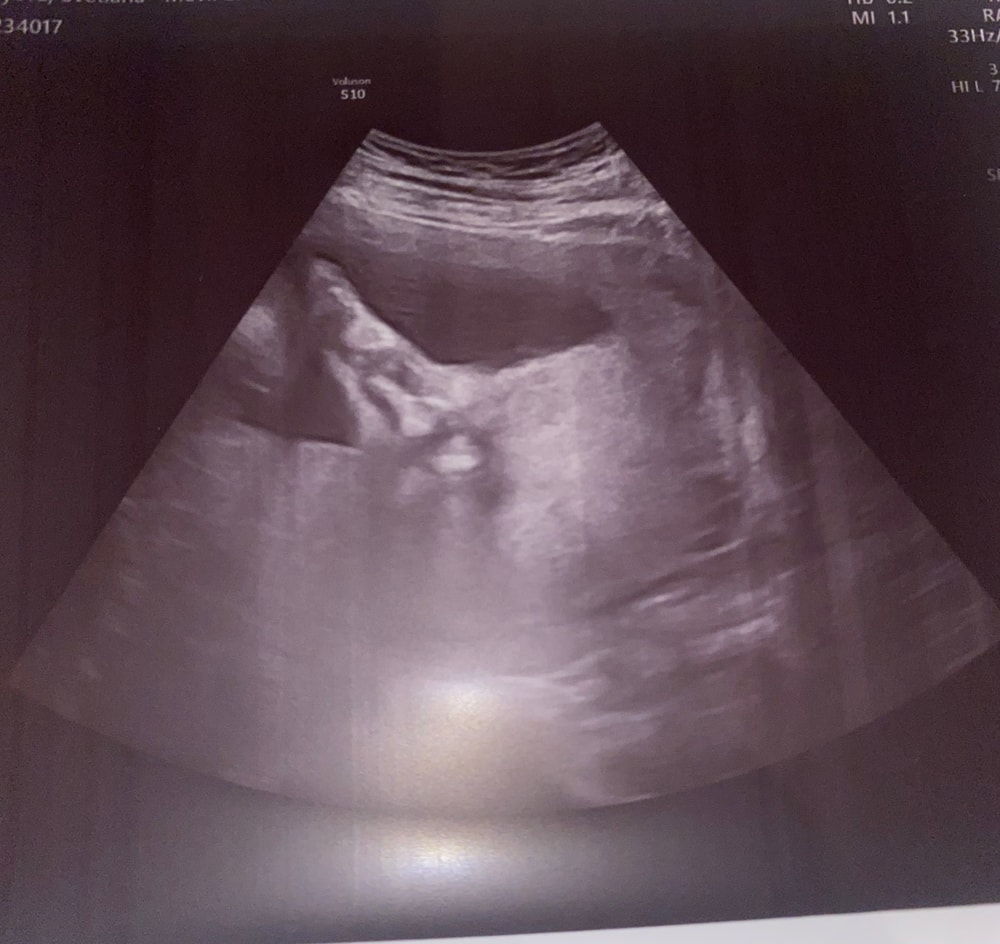

вчера была на контроле,ровно 29 недель -3ий триместр (врываемся в 30ую неделю),что сказать-вроде тьфу тьфу все хорошо,малая развивается в свои сроки,лежала в этот раз в не очень таком стандартном положении😁🫣 «поперек»уткнувшийся своими ножками в лицо 😆 доктор назвала ее « циркачкой»🥰 опять 3Д. не смогли снять….но за то «пяточку» очень хорошо сфоткали😁 Вес малышки -1500гр, рост не сказала, все окружности головы , тела, ножку соответствует 29 недели(+- пару дней вперед) похвалили нас с дочей наша замечательная врач , сказала что «гордиться нами» 🥰🥰🥰 На 27 недели сдавала тест на сахар - все в НОРмЕ👏Шевелюшки у нас с 17 недель ощущаемые ,сейчас она больше перекатывается , есть резкие толчки но не такие частые как раньше когда срок был меньше, и что интересно часто пульсация в низу живота ( врач сказала что это норма) когда она икает -это другое ощущение! Ну и чаще всего она с вечера и почти до утра мне устраивает перевороты😆

ну и самая сладкая ножка на свете ⤴️